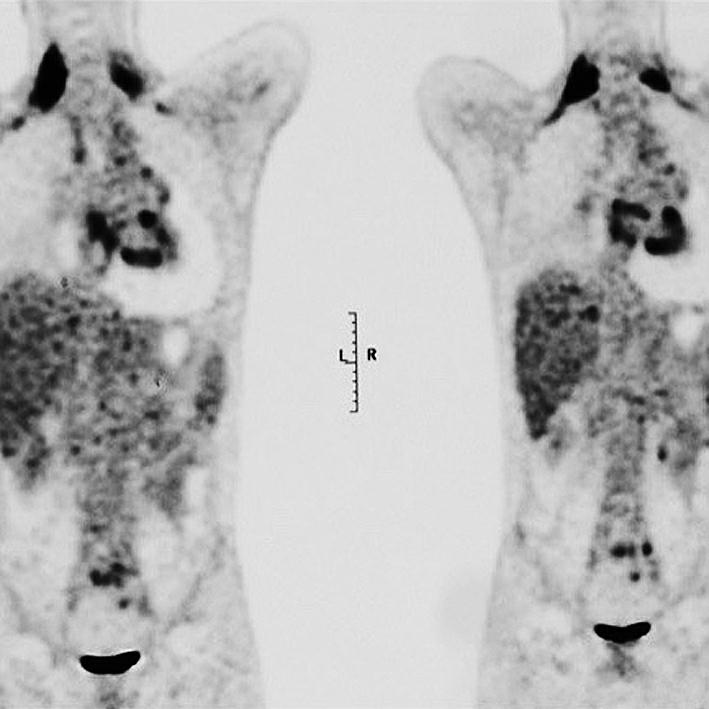

辅助检查:入院后行血常规、生化及结核与风湿免疫相关检验,均未见明显阳性结果,故考虑结核性心包积液可能性较小。后行心电图检查(2015年8月25日)示窦性心律,非特异性ST-T改变。X线胸片(2015年8月25日)示心影向双侧增大,呈烧瓶状。超声心动图(2015年9月1日)示舒张期心包腔内可见液性暗区:左室后壁21mm,右室前壁11mm,左室侧壁30mm,心尖20mm,右房顶10mm,剑突下20mm,心包腔内可见6.6cm×3.5cm实性团块,右室壁轻度受压(图1)。胸部增强CT(2015年8月26日)示心包腔内右心房上方见混杂密度肿块影,最大横截面积约6.1cm×4.0cm,病灶密度不均匀,伴有心包大量积液,少量右侧胸腔积液(图2)。心肌磁共振检查(2015年8月27日)示心包腔内团块状新生物,考虑恶性可能性大(图3)。随后在征得患者及其家属同意后,行PET-CT(2015年8月27日)检查,结果示心包腔内不均匀高代谢肿块,双侧颈根部及锁骨上窝多发高代谢肿大淋巴结,考虑恶性病变可能性大,伴随心包大量积液;右侧胸腔积液;腹、盆腔积液(图4)。综合以上检查及检验结果,考虑患者为恶性心包积液,心包腔内恶性病变可能性大,建议患者行穿刺活检,明确诊断。

图4PET-CT